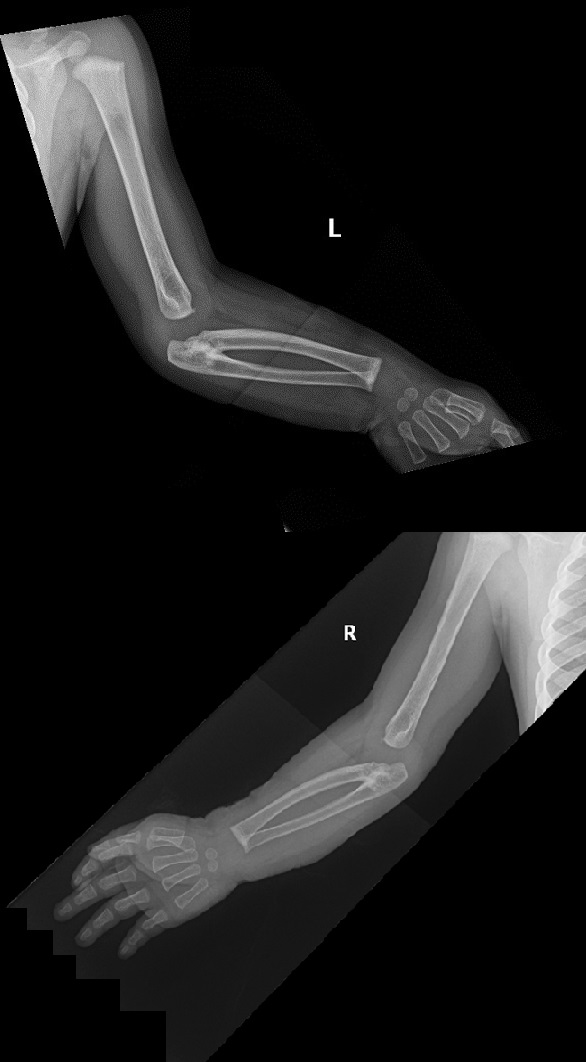

Se solicitó una radiografía de ambos brazos (Fig. 2) en la que se observó sinostosis radiocubital bilateral a nivel proximal, con ligera deformidad y subluxación de ambas cabezas femorales e incurvación diafisaria en los radios.

Figura 2. Radiografía de ambas extremidades: sinostosis radiocubital tipo II.

Nuestro caso correspondería a un tipo II. Clínicamente, son defectos que a veces pasan desapercibidos hasta los 3 o 4 años, cuando los padres o cuidadores observan cierto grado de dificultad para la supinación, como coger cubiertos, girar el pomo de las puertas, coger monedas o vestirse. El antebrazo se encuentra en pronación variable según la posición de la sinostosis. No conlleva una dificultad funcional importante, debido a que la persona, habitualmente, realiza movimientos compensadores con la articulación escapulohumeral, especialmente rotación externa y aducción, produciéndose, incluso, un aumento de los movimientos normales de esta articulación3. También suele existir hipermovilidad de la muñeca. En los casos bilaterales sin ningún grado de supinación, el grado de pronación es máximo y el paciente, en posición de firmes, tiene las palmas de las manos orientadas hacia atrás.